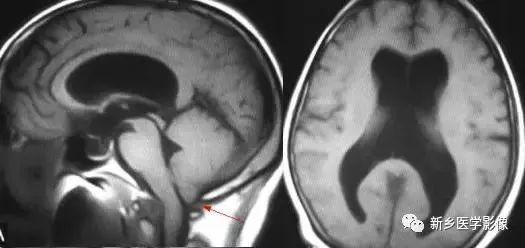

2.小脑扁桃体下疝畸形

又称Chiari’s畸形,即小脑扁桃体下移到椎管内,延髓、四脑室延长并部分向下移位。可分为3型。各型均常有脑积水表现。三脑室及侧脑室扩大。Ⅰ型:若仅有小脑扁桃体下移。扁桃体下缘低于枕大孔连线5mm以上,无脑干及四脑室改变者为Ⅰ型。Ⅱ型:除小脑扁桃体下移外,同时有四脑室部分或全部降入枕大孔以下者为Ⅱ型。Ⅲ型:全小脑及四脑疝入枕大孔以下者为Ⅲ型。